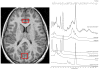

In this preliminary study, 16 psychotropic-naïve pediatric patients with obsessive-compulsive disorder (OCD) were studied using magnetic resonance spectroscopy (MRS) and genotyped for six candidate polymorphisms in two glutamate system genes. A significant association was identified between the rs1019385 polymorphism of the glutamate receptor, ionotropic, N-methyl-d-aspartate 2B (GRIN2B) and decreased anterior cingulate cortex (ACC) glutamatergic concentration (Glx) but not with occipital Glx. These results suggest that GRIN2B may be associated with Glx in the ACC, a region consistently implicated in OCD.